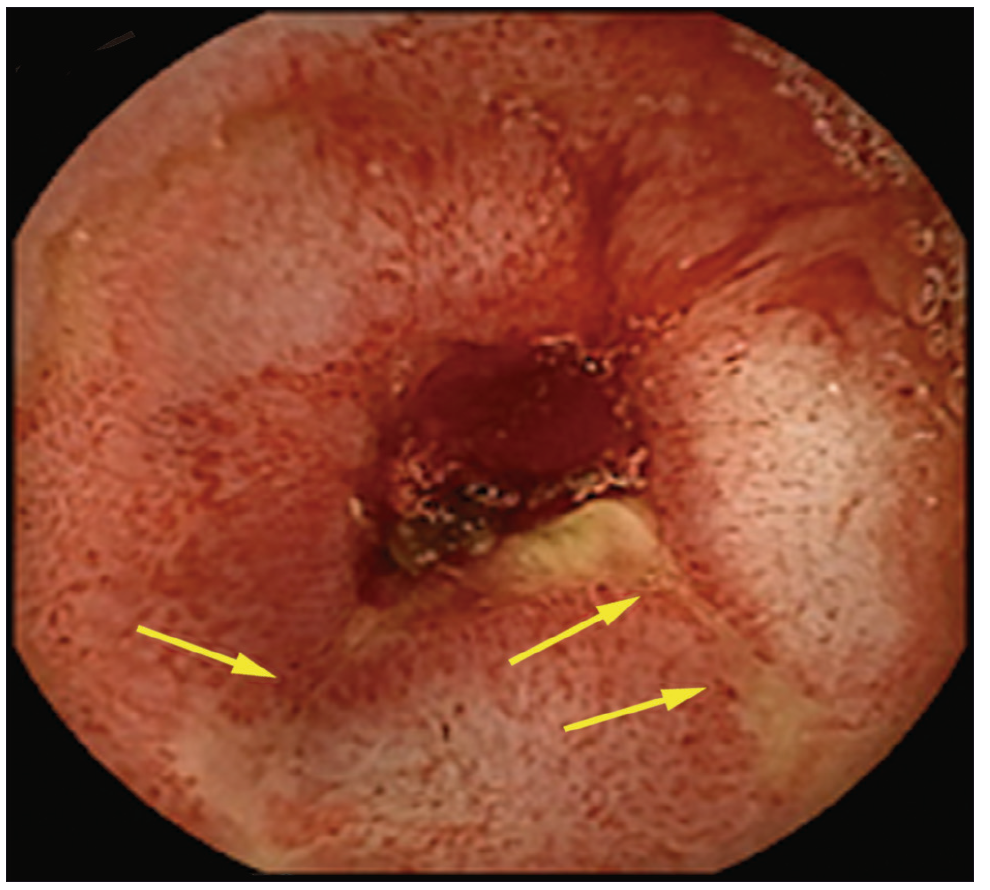

Con respecto a las imágenes, la radiografía directa de abdomen y la telerradiografía de tórax fueron normales. Se realizó una tomografía computada (TC) de abdomen que mostró asas de intestino delgado de paredes engrosadas sin estenosis, ausencia de líquido libre y presencia de divertículos en el colon. Se administraron hidratación y alimentación parenterales, y dos transfusiones de sangre. Se solicitó una videoendoscopía digestiva alta que evidenció gastropatía antral. En la videocolonoscopía hasta ciego se observó diverticulosis sigmoidea. Se constató la presencia de sangre fresca a través de la válvula íleocecal pero no se logró canular el íleon. Se solicitó una cápsula endoscópica (CE) donde se observó la presencia de sangre fresca y coágulos desde el yeyuno medio hasta íleon, con múltiples úlceras lineales, cicatrices y vasos de neo formación que alternaban con mucosa de aspecto normal (Figuras 1-3).

Figura 2. Úlcera ileal

Las zonas afectadas presentaban disminución del calibre de la luz intestinal. Dichos hallazgos eran compatibles con enfermedad de Crohn. No se observó el pasaje de la cápsula a colon a través de la válvula íleo cecal.